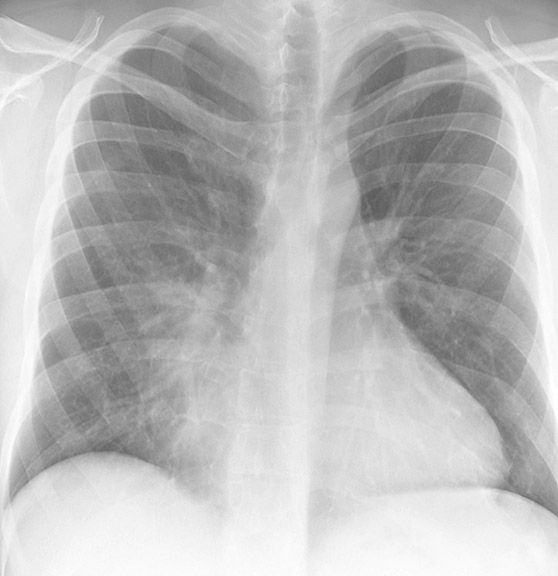

Gallery Lobar Collapse RML Collapse Case 2 PA

Case 2 PA